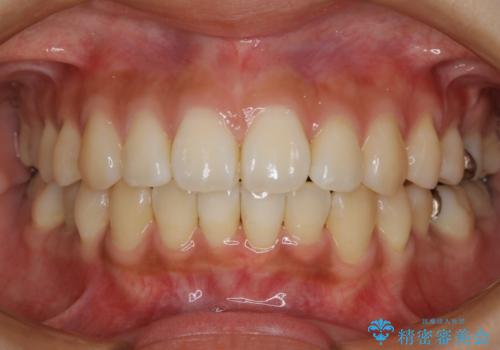

上下のデコボコを治したい インビザラインによる矯正治療